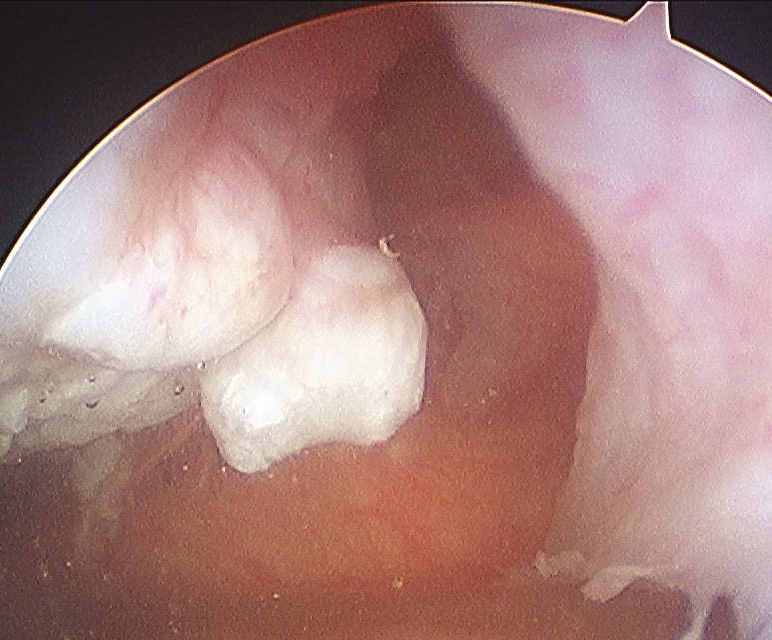

Osteochondral fracture (40-50%)

- LFC or medial facet patella

- patient will have haemarthrosis

- must identify this group, investigate and manage appropriately

2. Large Osteochondral Fragment

- usually medial patella or lateral femur